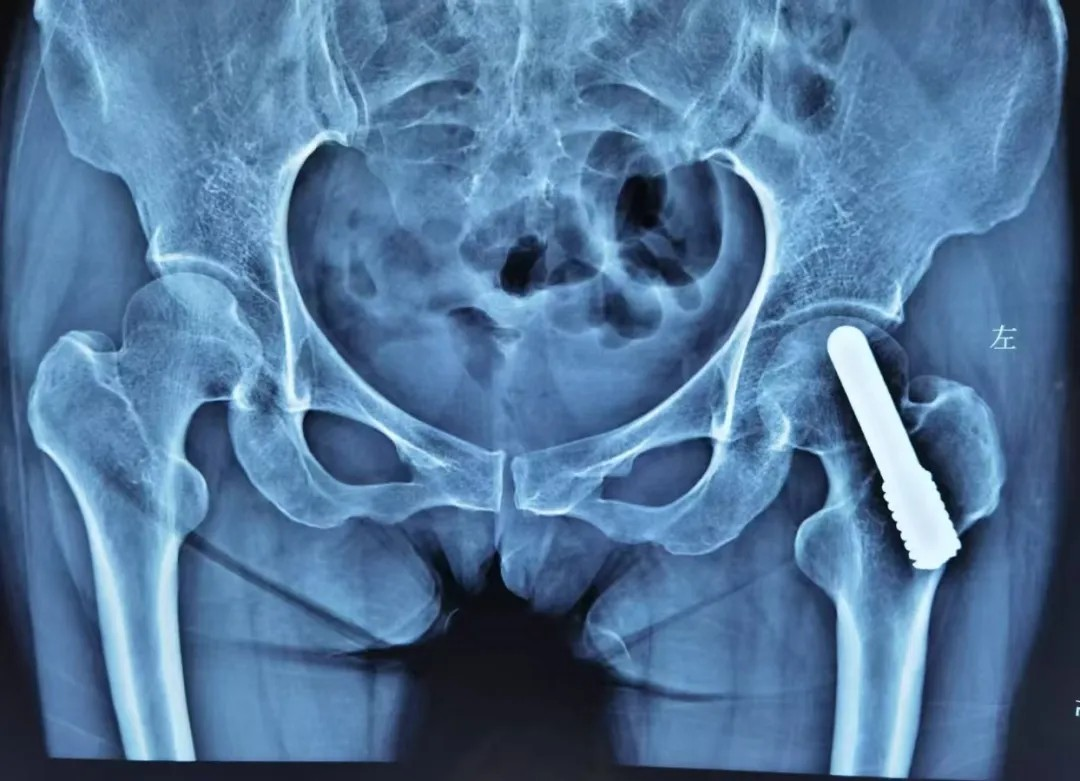

中(zhong)期:微創 “救” 股骨頭

股骨頭壞死中(zhong)期,此時股骨頭開始出現(xian)小(xiǎo)裂縫但沒塌陷,可(kě)以(yi)做微創保髋手術(shù),比如 “髓芯減壓術(shù)”(鑽小(xiǎo)孔減輕股骨頭內(nei)壓力(li))、“植骨術(shù)”(填入新(xin)骨促進(jin)修複),術(shù)後(hou)配(pei)郃(he)康複訓練,盡可(kě)能(néng)保留股骨頭功能(néng)。

若股骨頭塌陷輕微,還能(néng)嘗試 “截骨術(shù)”(調整股骨頭受力(li)位置);或采取钽棒置入術(shù),即在(zai)股骨頭中(zhong)放入钽棒,支撐壞死區(qu)域(yu)。